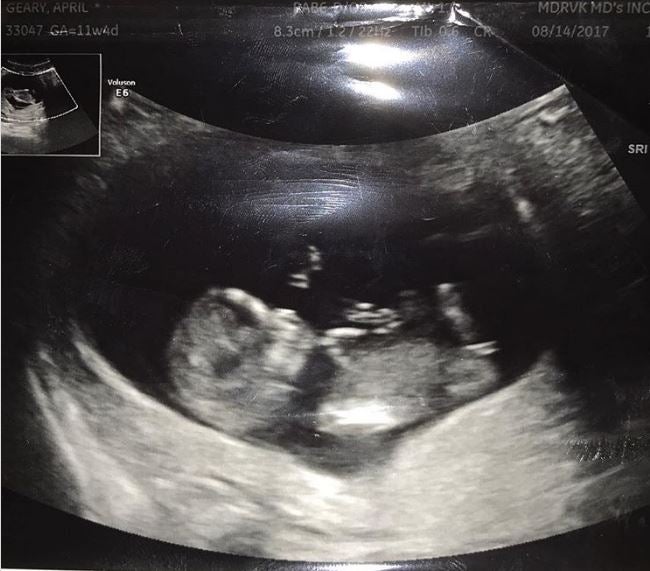

Com abordar el Trastorn de l'Espectre Alcohòlic Fetal?

Luisa María Conejos, subdirectora general d’addiccions, VIH, infeccions de transmissió sexual i hepatitis víriques de la Secretaria de Salut Pública, atén 'La Brúixola' per explicar el diagnòstic i les actuacions necessàries per abordar els casos de TEAF